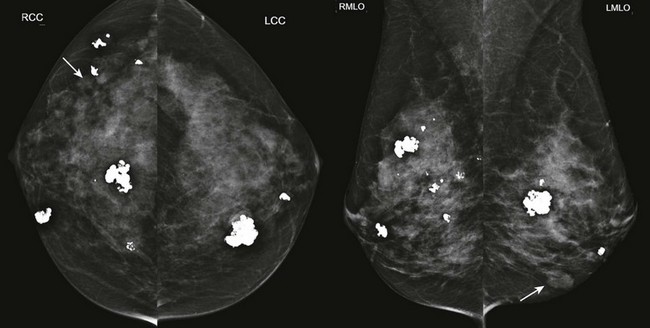

FIGURE 8-3 Multiple Fibroadenomas.

Screening mammogram on a 50-year-old woman. There are multiple bilateral masses, most with coarse calcifications typical of fibroadenomas. The noncalcified masses (arrows) likely represent fibroadenomas as well. The findings showed no suspicious changes for over 4 years.